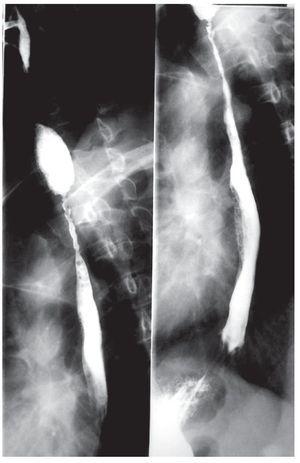

El paciente inició tratamiento con prednisona a dosis de 80 mg/día y azatioprina 100 mg/día con remisión del cuadro cutáneo y oral. Sin embargo, presentó odinofagia y disfagia progresiva, por lo que fue solicitada una endoscopía digestiva alta, que reportó la presencia de adherencias en la hipofaringe, sin posibilidad de abordaje esofágico. Fue enviado al Servicio de Otorrinolaringología y Fonoaudiología para la sección de las adherencias sin obtener mejoría clínica significativa. El paciente presentó progresión de la disfagia para líquidos y pérdida de 18.5 kg de peso hasta alcanzar un índice de masa corporal de 22.5 kg/m2. Se efectuó un estudio dinámico de la deglución, que evidenció disfagia moderada para sólidos y para volúmenes mayores de 10 mL, sin encontrar lesiones bulosas activas en la hipofaringe. El estudio con medio de contraste (bario) del esófago, demostró estenosis segmentaria irregular en el tercio proximal y medio del esófago (Figura 3). Fue transferido al Servicio de Endoscopía Gastrointestinal del HCFMUSP para tratamiento endoscópico con dilatadores.

¿ Figura 3. Esofagograma que muestra estenosis segmentaria en el esófago proximal.